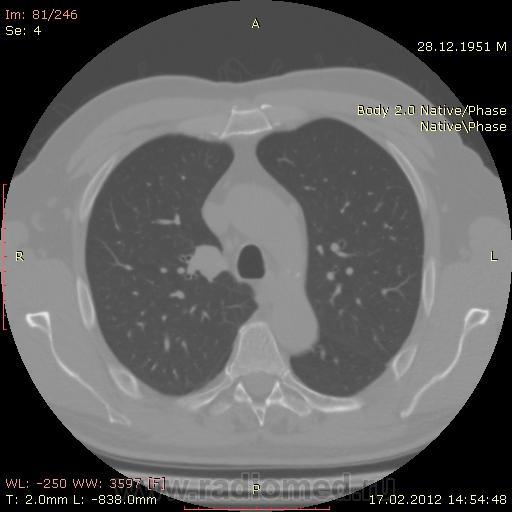

КТ.

В феврале 2012 года при очередном флюрографическом обследовании были обнаружены изменения в лёгких. По собственной инициативе было сделано КТ лёгких.